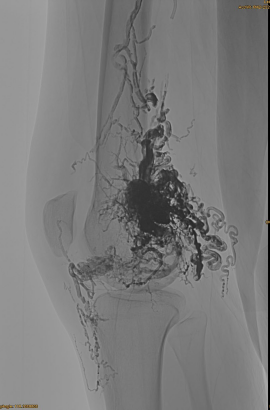

रोगी की बुनियादी जानकारी: महिला, 36 वर्ष; एवीएम पेल्विस, हिप, घुटने, बाएं ओएसजी, कई पूर्व - एम्बोलिज़ेशन।

प्रारंभिक डीएसए:

अंतिम परिणाम:

शायद ही कोई शिरापरक बहिर्वाह:

देर से चरण, एक और EMBO आवश्यक है, लेकिन बहुत बेहतर: